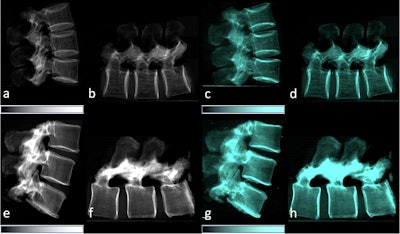

Lateral conventional attenuation (a, b, e, f) and co-registered dark-field (c, d, g, h) images of two spine specimens. Vertical (a, c, e, g) and horizontal (b, d, f, h) scans of the spine specimen of a 77-year-old female with osteoporosis (bone mineral density = 65.75 mg/dL) (a–d) and a non-osteoporotic spine specimen (e–h) of a 61-year-old female (bone mineral density = 169.38 mg/dL).Image available for republishing under Creative Commons license (CC BY 4.0 DEED, Attribution 4.0 International) and courtesy of European Radiology Experimental.

The team found that the dark-field signal was significantly lower in the osteoporotic/osteopenic vertebrae compared to non-osteoporotic/osteopenic samples for both the vertical and horizontal orientation, and it correlated significantly with the CT measurements.

Specifically, the researchers found a significant positive correlation between the dark-field signal from the vertical position with trabecular number (p = 0.005), bone volume fraction (p = 0.007), degree of anisotropy (p = 0.01), and hydroxyapatite density (p = 0.01).

In addition, the calculated ratio of the vertical/horizontal dark-field signal also correlated significantly with trabecular number (p = 0.011), bone volume fraction (p = 0.032), degree of anisotropy (p = 0.002), and hydroxyapatite density (p = 0.049).